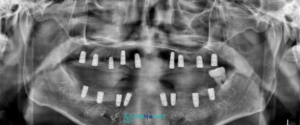

이를 위해 수술 후 일상으로의

복귀가 보다 원활하도록,

컴퓨터 가이드 임플란트를 통해

식립을 진행하기로 하였습니다.

망원동치과 365바른약속치과에서는

환자분의 구강 상태를 디지털 장비를 통해

면밀하게 확인한 뒤,

시뮬레이션 결과를 바탕으로

가이드를 제작하여 컴퓨터 가이드

임플란트 식립을 진행하였습니다.